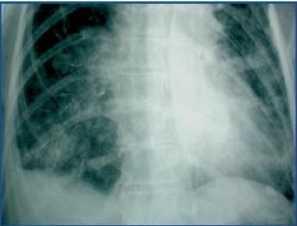

Se trata de una paciente mujer de 54 años con antecedentes de hipertensión e insuficiencia renal crónica no filiada en programa de diálisis peritoneal desde hacía 8 meses, que fue ingresada en nuestro servicio por diarrea con hipotensión y un episodio de rectorragia. El examen físico abdominal fue irrelevante. Los hallazgos analíticos mostraron hiperamilasemia cerca de 900 U/l (42-220 U/l) con leucocitosis de 22,1 X 109 l. Los demás parámetros de laboratorio estaban en rango de la normalidad. Se analizó el líquido peritoneal descartando peritonitis. La radiografía simple abdomen (figura 1) mostró opacificaciones difusas en colon que correspondían a los comprimidos de carbonato de lantano introducidos 2 meses antes del ingreso como tratamiento de la hiperfosfatemia (0,75 g oral 3/día). Se practicaron dos colonoscopias sin éxito que informaban de pobre preparación y un stop en la progresión del colonoscopio. En una tomografía computarizada abdominal se detectó la presencia de un fecaloma impactado en el área rectosigmoidal. No se evidenciaron masas patológicas pancreáticas ni en el resto del abdomen. El fecaloma pudo ser extraído y el mismo día la paciente presentó disnea brusca y empeoramiento del estado general con hipotensión y desaturación de oxígeno. En la radiografía simple de tórax (figura 2) se observaron líneas radioopacas siguiendo los alvéolos pulmonares. Se reinterrogó a la familia confirmando la administración de los comprimidos de Lantano suspendidos en el ingreso. La paciente fue hemodializada sin mejoría del cuadro pulmonar y falleció.

Figura 1.